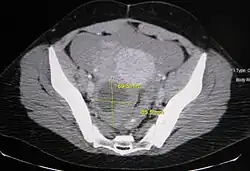

Diagnosis

Ovarian cysts are usually diagnosed by pelvic ultrasound, CT scan, or MRI, and correlated with clinical presentation and endocrinologic tests as appropriate.[15] Ultrasound is the most important imaging modality, as abnormalities seen in a CT scan sometimes prove to be normal in ultrasound.[5][8] If a different modality is needed, then MRIs are more reliable than CT scans.[5]

Ovarian cysts are considered large when they are over 5 cm and giant when they are over 15 cm. In children, ovarian cysts reaching above the level of the umbilicus are considered giant.